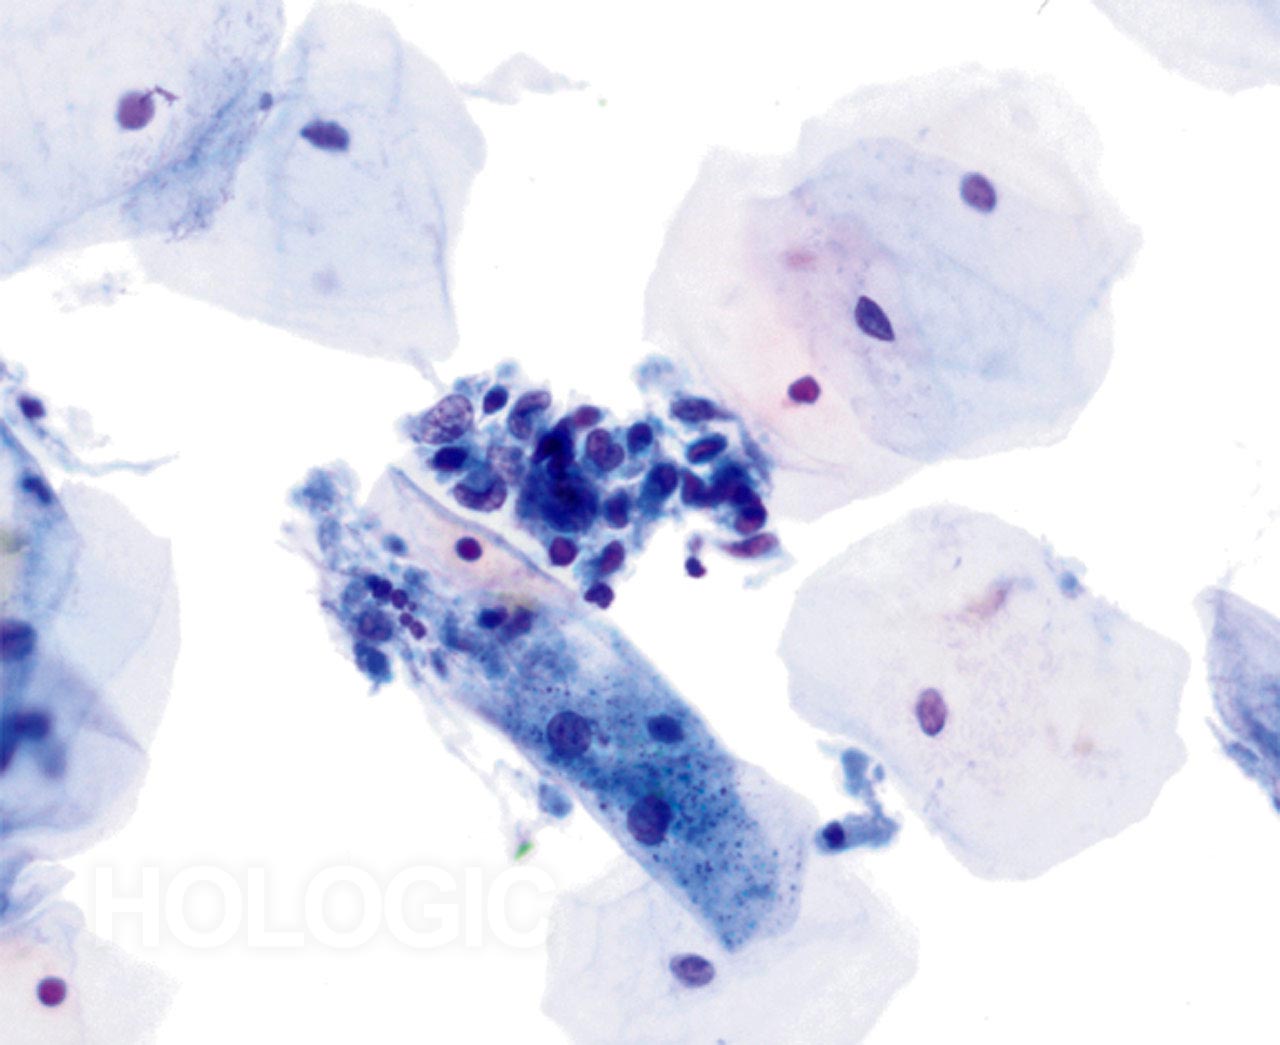

Cytolyse

Le motif familier des noyaux nus, des cellules superficielles/intermédiaires et des bacilles de Döderlein associés à la cytolyse induite par des lactobacilles est facilement identifiable à faible grossissement sur des lames ThinPrep. Les bacilles peuvent être enfermés dans du mucus ou recouvrir des cellules malpighiennes.